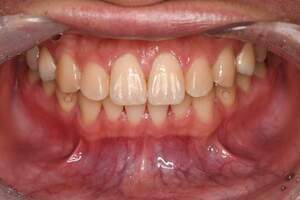

歯石除去・PMTC

治療前

治療後

| 年齢 | 52歳・男性 |

|---|---|

| 主訴 | クリーニング希望 治療部位:全顎 |

| 治療内容 | 初診検査 歯石除去(保険診療) PMTC(自費診療) |

| 治療期間 | 60分 |

| 費用 | 合計約10,500円 初診検査約3,000~4,000円 歯石除去約1,000円 PMTC5,500円(自費診療) (2024年2月現在) (歯の本数や検査内容で料金が変動します。) |

| リスク・副作用 | ・歯ぐきの炎症がある場合は歯石除去中に出血を伴う可能性があります。 ・処置後、知覚過敏がおこる可能性があります。 ・歯石除去後、炎症が治ると歯ぐきが引き締まる為、歯が長くなったように感じることがあります。 |

| 治療方針 | 全顎的に歯石除去後、PMTCにて着色とバイオフィルムを除去。 |

| 特記事項 | ・3年ぶりの歯科医院 ・1日に3杯程度コーヒーを飲む |

| 担当者所見 | 下の前歯の裏側(舌側)に歯間を埋めるように歯石がついていました。 歯間の歯石がなくなると、舌で触った時に気になっていたざらつきもなくなり、すっきりしたと喜んでくださいました。 |